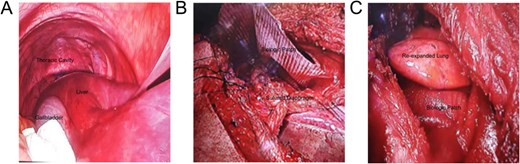

The patient's organs had been in an abnormal position for an extended period, causing significant friction between organs due to breathing and daily activities, leading to severe adhesions. Preoperative CT showed that the liver was almost entirely located within the right thoracic cavity (Fig. 2A), which was further confirmed through advanced laparoscopic exploration during surgery. The surgery began with an abdominal procedure, where adhesiolysis was performed, and the right triangular ligament of the liver was incised to mobilize the liver and prevent it from retracting back into the thoracic cavity. Following this, a thoracic procedure was performed to separate the liver from its adhesions to the pericardium. To repair the diaphragmatic defect, non-absorbable Ethibond sutures were used for closure, and a 15 cm × 20 cm composite mesh was placed on the thoracic side, secured with lateral staples and medial sutures (Fig. 2B). After the diaphragm repair, lung inflation demonstrated satisfactory re-expansion of the right lung (Fig. 2C). An intercostal drainage tube was placed at the surgical site to prevent postoperative pleural effusion. The surgery was completed smoothly, and the patient was transferred to the intensive care unit for further monitoring.

Intraoperative images: (A) Laparoscopic view showing the liver herniated into the right thoracic cavity; (B) Diaphragm repair to secure the mesh; (C) Successful re-expansion of the right lung.